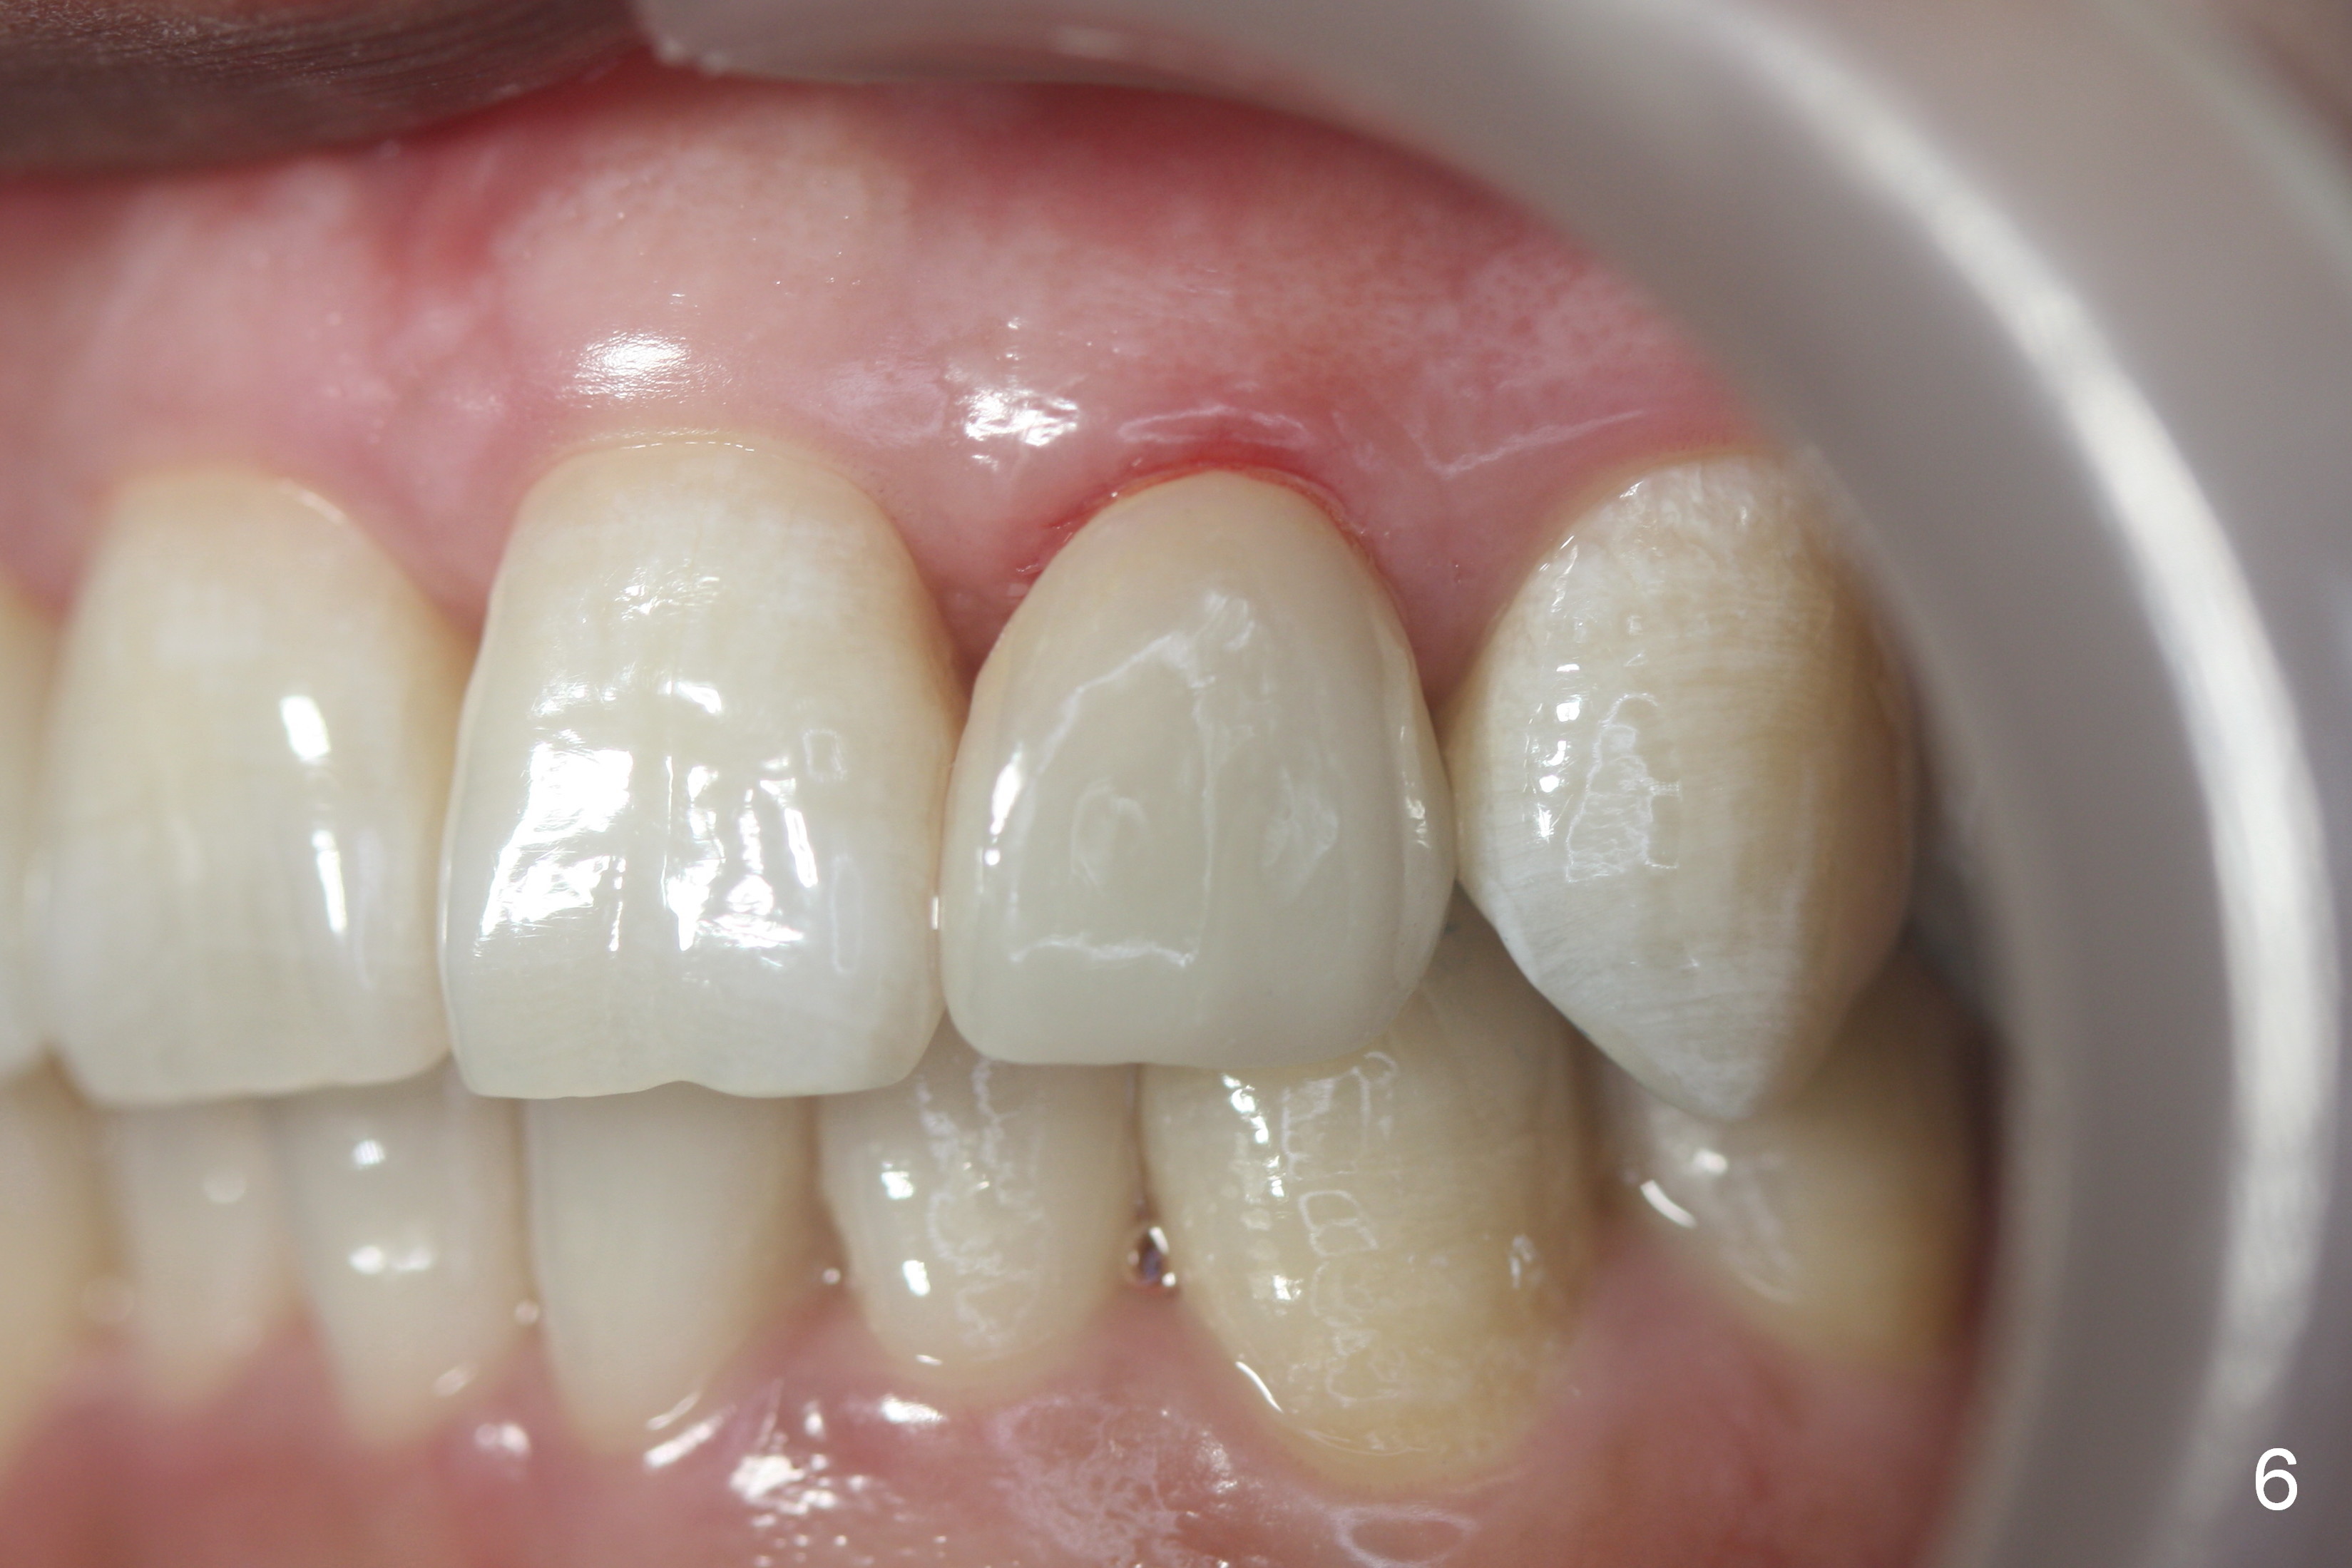

| After |

A 36-year-old man has 2 small, congenitally deformed lateral incisors (peg laterals, Fig.1,2 *). After discussion, we choose porcelain veneers for cosmetic makeup. The teeth need minor shaving (Fig.3,4); right colors are being selected with a shade guide (Fig.4: G). The shaving is so conservative that there is no pain during the procedure and there is no need to make temporary veneers. One to 2 weeks later, porcelain veneers are cemented (Fig.5,6). The patient is satisfied.